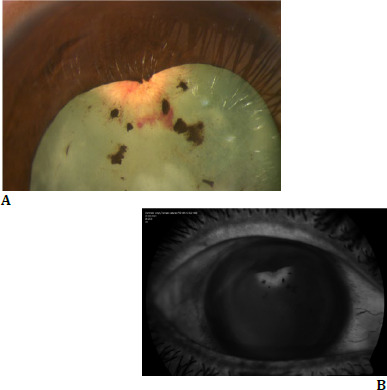

Patient and clinical findings: A male patient, 27, presented with a severe reduction in vision in his right eye (RE) accompanied by redness for one month. He also had a distant history of blunt trauma to the RE approximately eight years before. His vision in the RE was reduced to hand motion and 20/20 in the left eye. Examining the anterior segment in RE revealed lenticular neovascularization, irregular anterior capsular thickening, iris sphincter tear at the 12 o'clock position, and fine KPs, with iris pigment clumps on the anterior capsule.

Diagnosis treatment and results: To reduce vascularization and inflammation, the patient was treated with intravitreal Anti-VEGF and suprachoroidal triamcinolone by an innovative technique, along with cataract surgery, following which visual acuity improved to 20/20.